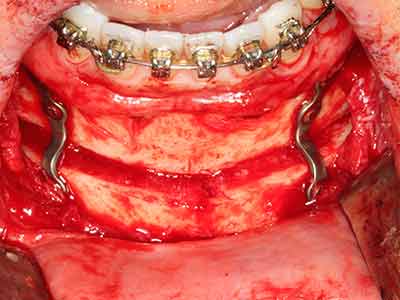

Фиг. 1: Препарация на костно покритие с Piezomed (W&H Залцбург, Австрия).

Фиг. 6: След препарация на мукопериосталната клапа.